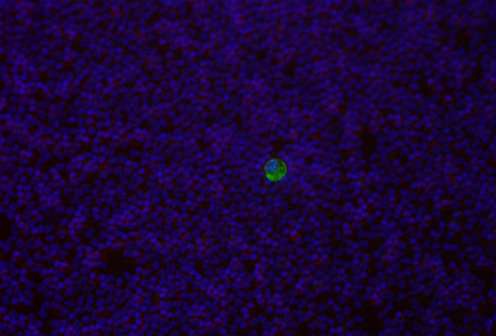

Immagine: Una cellula del cncro colorata con rVAR2 (verde) in uno sfondo di globuli bianchi normali (rosso). Credito: Università di Copenaghen.